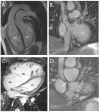

Cardiovascular magnetic resonance (CMR) has expanded its role in the diagnosis and management of congenital heart disease (CHD) and acquired heart disease in pediatric patients. Ongoing technological advancements in both data acquisition and data presentation have enabled CMR to be integrated into clinical practice with increasing understanding of the advantages and limitations of the technique by pediatric cardiologists and congenital heart surgeons. Importantly, the combination of exquisite 3D anatomy with physiological data enables CMR to provide a unique perspective for the management of many patients with CHD. Imaging small children with CHD is challenging, and in this article we will review the technical adjustments, imaging protocols and application of CMR in the pediatric population.